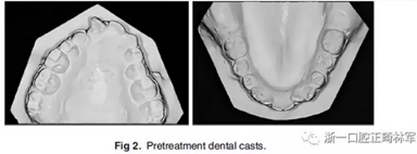

咬合關(guān)系:右側(cè)磨牙有II類關(guān)系傾向,尖牙關(guān)系II類;左側(cè)磨牙關(guān)系完全I(xiàn)I類,尖牙關(guān)系I類。上頜雙側(cè)反合,中線稍有偏離。覆合、覆蓋減少。上頜中切牙向腭裂側(cè)旋轉(zhuǎn),上頜右側(cè)尖牙頰側(cè)異位萌出,雙側(cè)乳尖牙仍存在?;颊呱项M弓嚴(yán)重?fù)頂D(擁擠度約10mm),下頜弓輕度擁擠4mm(擁擠度約4mm)(圖1 ;圖2)。牙周檢查良好。